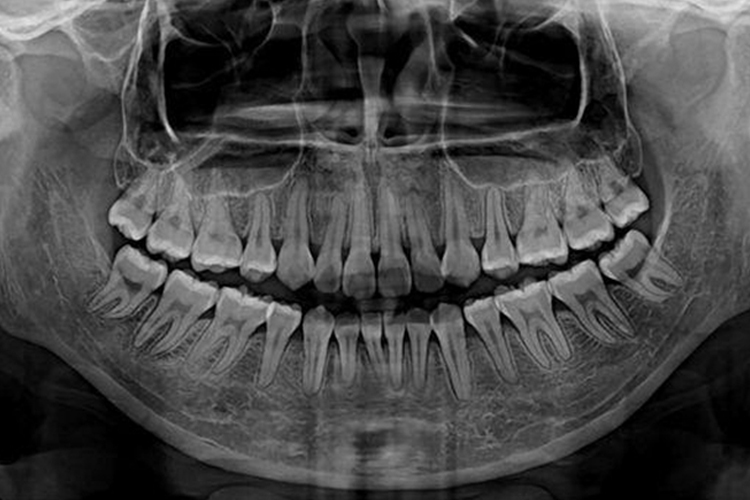

牙齿CT通常是指CBCT,即锥形束CT,标准锥形束CT可清楚显示患者颌骨、牙齿以及颞下颌关节等硬组织结构,在三维重建图像上通过调节窗去除部分骨组织,只留下密度更高的牙齿图像,可清晰显示骨内埋伏牙与邻牙空间位置关系。此外,CBCT还可拍摄口腔全景片,可以在一张全景图上观察全部牙齿的情况。